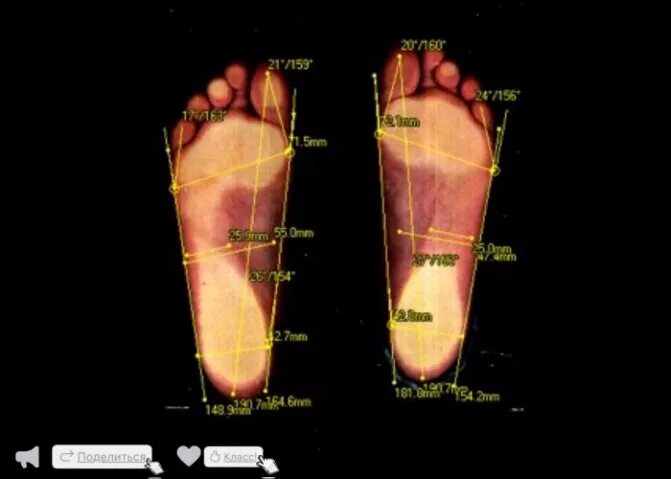

Состояние стопПлоскостопие плантограмма. плантография стопы с плоскостопием. плантограмма стопы при плоскостопии. выявление плоскостопия по отпечатку стопы.Состояние стопПоперечное плоскостопие 2 степени. продольное плоскостопие 2. продольно-поперечное плоскостопие 2 степени. плантография 3 степень плоскостопия.Продольное поперечное и комбинированное плоскостопие. степени стопы на плоскостопие. продольное и поперечное плоскостопие 2 степени. продольно-поперечное плоскостопие и вальгус 3 степени.Продольное плоскостопие 2. продольное плоскостопие 3 степени. стопа с плоскостопием 3 степени. ploskostopiye.Продольно-поперечное плоскостопие 3 степени. продольное и поперечное плоскостопие 3 степени. поперечное плоскостопие 2-3 степени. плоскостопие 4-ой степени.Метод выявления плоскостопия. метод измерения плоскостопия. метод выявления плоскостопия у детей. плоскостопие по отпечатку стопы метод.Состояние стопСостояние стопПлантограмма продольное плоскостопие. продольное и поперечное плоскостопие. степени продольного и поперечного плоскостопия. продольное и поперечное плоскостопие 3 степени.Плоскостопие. строение детской стопы. плавание при плоскостопии. особенности стопы.Отпечаток стопы при плоскостопии 3 степени. продольное и поперечное плоскостопие. отпечатки ног при плоскостопии у детей. след стопы человека с плоскостопием.Плоскостопие 2-3 степени. симптомы продольного и поперечного плоскостопия. плантография поперечного плоскостопия. поперечное плоскостопие отпечаток стопы.Степени плоскостопия у детей. плантограмма при поперечном плоскостопии. продольное плоскостопие. тип стопы плоскостопие.Ploskostopiye. плоскостопия. плоскостопие у взрослых. плоскостопие симптомы у взрослых.Отпечаток нормальной стопы. нормальная стопа человека. след плоскостопия. отпечаток стопы при плоскостопии.Эквиноварусная деформация стоп. варусная постановка стопы у ребенка. отпечаток стопы при плоскостопии 3 степени. эквиноварусная деформация стопы у детей.Состояние стопПлантограмма продольное плоскостопие. плантография стопы при плоскостопии. плантограмма при поперечном плоскостопии. плантография стопы расшифровка.Метод выявления плоскостопия. обследование на плоскостопие. методы исследования плоскостопия у детей. исследования сводов стопы.Формирование свода стопы. формирование свода стопы начинается. стопа ребенка в 3 года плоскостопие. формирование свода стопы заканчивается.Состояние стопОценка поперечного свода стопы. продольное плоскостопие - уплощение продольного свода стопы. оценка продольного свода стопы. оценка степени уплощения поперечного свода.Плоскостопие степени причины. симптомы плоскостопия у детей. плоскостопие симптомы у взрослых. степени развития плоскостопия.Самодиагностика. самодиагностика человека. самодиагностика стоп. самодиагностика женщина.Состояние стопСостояние стопПлантография 3 степень плоскостопия. отпечаток стопы 3 степени плоскостопия. след ноги при различных степенях плоскостопия.. плоскостопие 4-ой степени.Плоскостопие и позвоночник. плоскостопие нагрузка на позвоночник. плоскостопие и тазобедренный сустав. плоскостопие и позвоночник связь.Плантография степени плоскостопия. отпечаток стопы норма и плоскостопие. плантограмма продольное плоскостопие. плантография поперечного плоскостопия.Состояние стопСостояние стопСтопа плоскостопие 2 степени. показатели третьей степени плоскостопия. лечится ли плоскостопие 1 степени у взрослых. плоскостопие 3 степени вид сбоку.Состояние стопПоперечное плоскостопие плоская стопа. симптомы продольного и поперечного плоскостопия. поперечное плоскостопие симптомы у взрослых. плоскостопие симптомы у взрослых.Сводчатая стопа и плоскостопие. возраст формирования свода стопы у ребенка. степень развития свода стопы. свод стопы у ребенка формируется к.Чешуйчатое состояние стопы. артритможет воспалиься отмышьяка. правда ли что стопы расскажут о состоянии организма.Точки на стопе отвечающие за органы. болевые точки на стопе. активные точки на стопе. точки здоровья на стопе человека.Симптомы продольного и поперечного плоскостопия. вид стопы с поперечным плоскостопием. распластанность переднего отдела стопы (поперечное плоскостопие). поперечное плоскостопие клинические рекомендации.